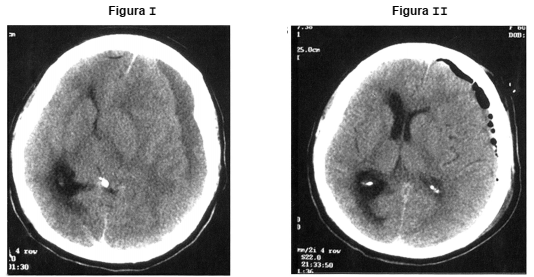

Homem de 66 anos apresentou rebaixamento de nível de consciência e episódio convulsivo. Abaixo, a Figura I mostra a tomografia de crânio na admissão e a Figura II após tratamento.

A conduta terapêutica fundamental provavelmente foi